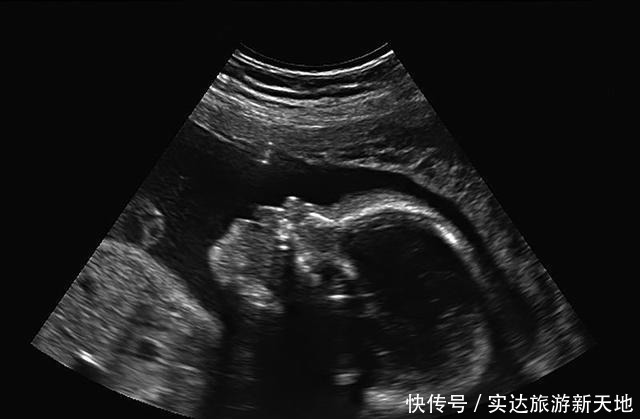

2、宝宝的NT检查数值NT检查是指宝宝颈部的空隙位置的颈项透明层厚度。正常情况下,这里应该是透明的,因为这是宝宝新陈代谢所产生的积液,是对宝宝的一种保护。NT检查目的是在孕妇怀孕初期来诊断宝宝是否有染色体疾病,比如21三体综合征等胎儿异常,是早期排除宝宝是否发育正常的检查。

NT检查一般在孕妇怀孕3个月左右去做的检查。宝宝NT的正常厚度是要小于3mm的。如果NT检查的结果显示厚度大于3mm,这就警示我们要注意:胎儿发育可能不是那么健康。在检查报告中,一般也会显示胎儿的染色体是否存在异常现象,胎儿发育是否健康,没有畸形。孕妇后面还会做唐氏筛查来排查宝宝是否发育良好,医生也会重点关注,必要时孕妇可以多做些检查综合判断,例如无创DNA检查、羊水穿刺检查、胎儿染色体检查等。